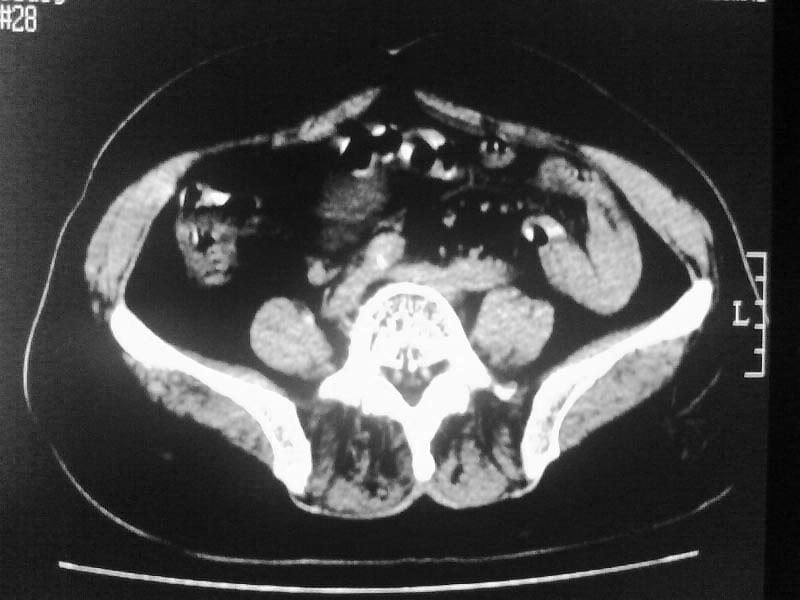

标题: CT20044:女,45岁,腰痛2年,双肾结石,右输尿管结石,右肾重度积 [打印本页]

标题: CT20044:女,45岁,腰痛2年,双肾结石,右输尿管结石,右肾重度积

支持双肾结石、右输尿管上端结石,右肾重度积水

右肾梗阻性积水。

支持 右肾结石、右输尿管上端结石,右肾重度积水。

双肾结石、双输尿管结石并右肾积水。

双肾,输尿管结石,右肾重度积水。